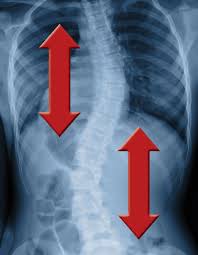

Scoliosis And Yoga The Do S And Don Ts Scoliosis Exercises Scoliosis Scoliosis Exercises Yoga